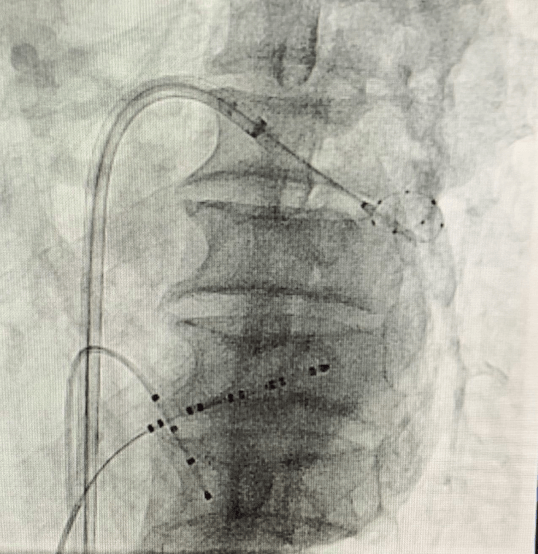

(手术过程)